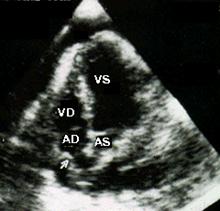

Semne ecocardiografice:

lichid pericardic in cantitate mare (evidentiaza si dispunerea topografica a acestuia),

reducere a amplitudinii excursiei DE si pantei EF a valvei mitrale la prima diastola din inspir,

variatie inspir-expir > 40% a amplitudinii excursiei DE a valvei tricuspide,

colaps AD, VD (protodiastolic) si AS,

congestie 'fixa' a VCI (scadere < 50% in diametru proximal la inspir profund).

EcoCG in tamponada cardiaca